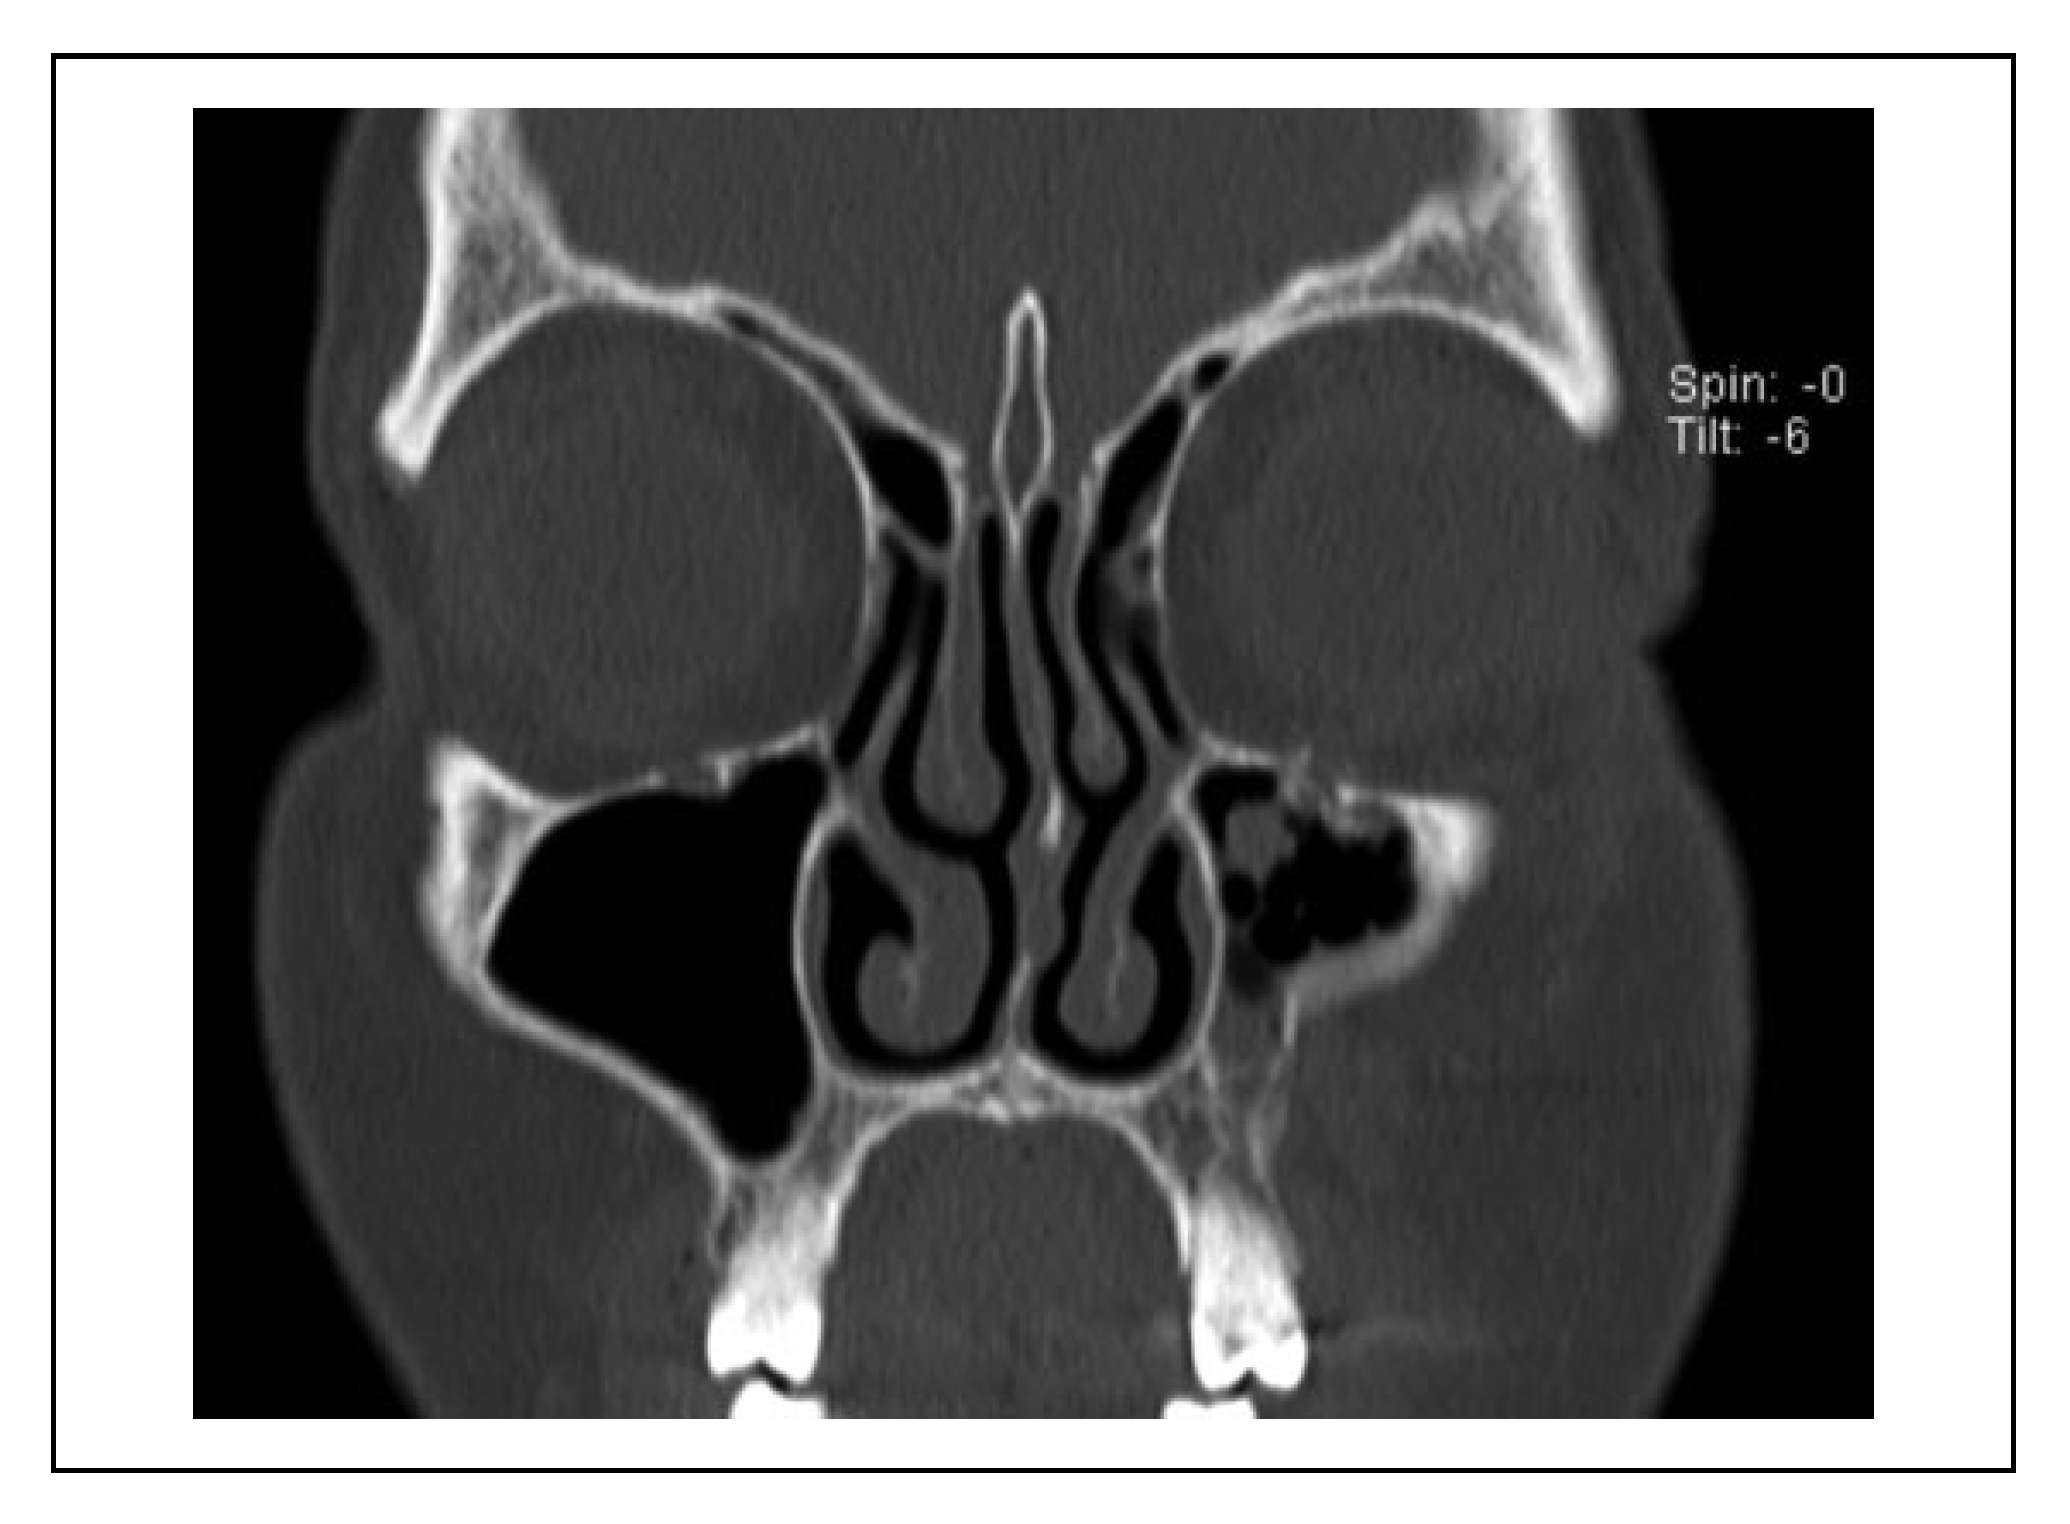

A case was considered to show involvement of the fracture course through the infraorbital canal (IOC) when the fracture line penetrated the cortex of the IOC at one site or more (Figure 2). When the fracture line was near the IOC (within 1 mm), this indicated that the cortex of the IOC was still intact (Figure 3).

Figure 3. Patient with a left zygomaticomaxillary complex fracture with the fracture line near the infraorbital canal (within 1 mm), and an intact cortex of the infraorbital canal. This patient did not experience hypoesthesia of the infraorbital nerve.